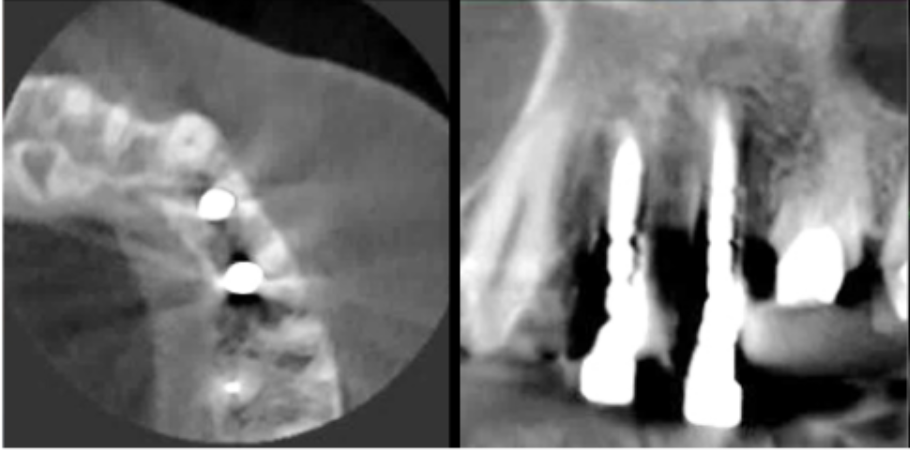

インプラント

サージカルガイドの作成

インプラント埋入前のCTによる確認